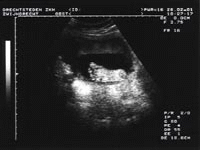

praktijk voor echografie in de zwangerschap

Echo Visie is gespecialiseerd in het maken van zwangerschapsecho's. De onderzoeken worden verricht door een zeer ervaren echoscopiste (FMF gecertificeerd voor nekplooimetingen en structureel echoscopisch onderzoek bij 19-22 weken: www.fetalmedicine.nl, diploma Post-HBO opleiding echografie Fontys Hogeschool Eindhoven).

26 jaar werkzaam geweest als echoscopiste gynaecologie verloskunde in het Albert Schweitzer Ziekenhuis te Zwijndrecht.